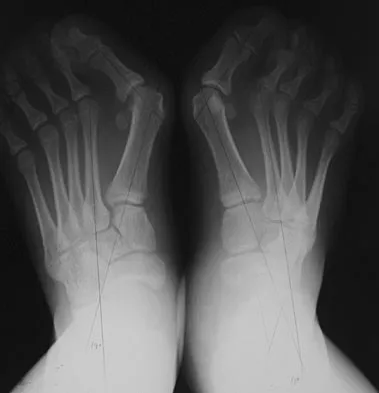

An active 47-year-old woman with rheumatoid arthritis reports forefoot pain and deformity and has difficulty with shoe wear. Examination reveals hallux valgus and claw toes. A radiograph is shown in Figure 10. What is the most appropriate surgical treatment?

Explanation

Rheumatoid arthritis commonly affects the metatarsophalangeal joints, which become destabilized with time resulting in hallux valgus and dislocated lesser claw toes. The result is metatarsalgia as the dislocated claw toes "pull" the fat pad distally. Severe hallux valgus reduces first ray load, which compounds the metatarsalgia because the load is transferred to the lesser metatarsal heads. First metatarsophalangeal arthrodesis restores weight bearing medially and corrects the painful bunion. Metatarsal head resection slackens the toe tendons to allow correction of the claw toes by whatever means necessary and decreases plantar load over the forefoot. Rheumatoid arthritis in the first metatarsophalangeal joint will continue to progress if osteotomies or a Lapidus procedure are performed. Keller resection arthroplasty increases transfer metatarsalgia and reduces push-off power during gait. Flexor-to-extensor tendon transfer of the lesser toes does not address the metatarsalgia and does not correct the dislocation of the metatarsophalangeal joint. Coughlin MJ: Arthritides, in Coughlin MJ, Mann RA (eds): Surgery of the Foot and Ankle, ed 7. St Louis, MO, Mosby, 1999, p 572.